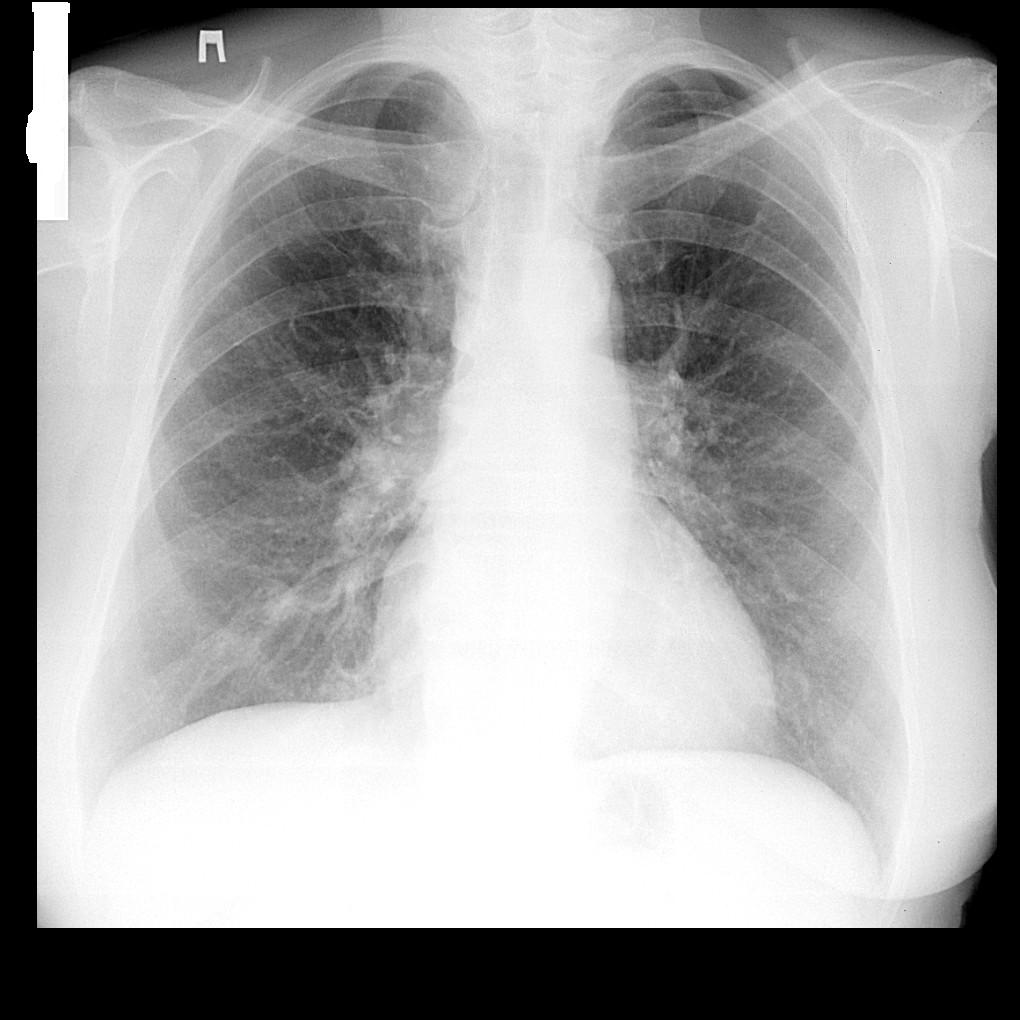

Локальное усиление пневмофиброза здесь симптом совершенно малозначительный. Что-то есть в S9 и в S4. Существеннее тут расширение и ухудшение структурности корней, особенно правого.

Думаю, что игра ЛР и ребер. А корни не смущают?

Локальное усиление пневмофиброза

В каком сегменте? Или его усиление, фиброза-то... чем бы это ни было)